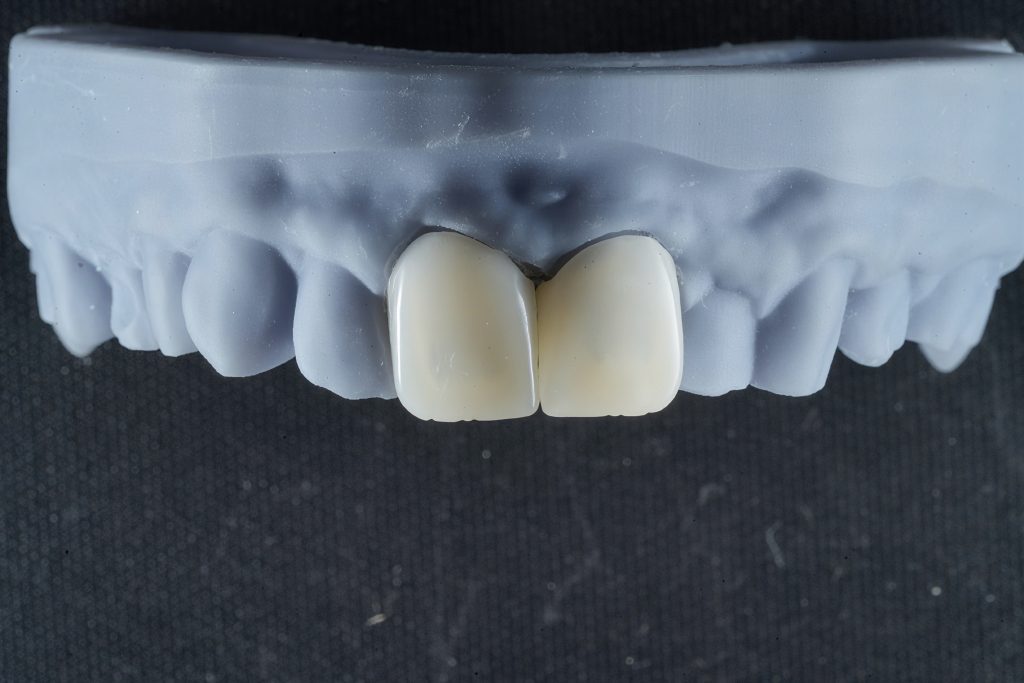

Step 2 — Digital Smile Design & Exocad Workflow

A full digital workflow was used:

- Intraoral scanning

- DSD-based analysis for ideal tooth proportions

- Exocad 3D designing of width/height ratio, incisal embrasures, line angles

- 3D printed mock-up for physical evaluation

This allowed previewing the final aesthetic and functional outcome before touching the tooth.